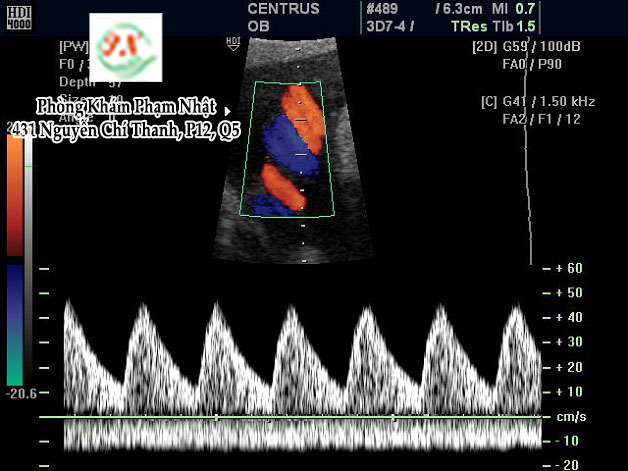

Tỷ lệ vận tốc cuối tâm thu và tâm trương (S/D ratio) cung cấp thông tin về kháng lực mạch máu trong bánh nhau. Bình thường S/D ratio giảm dần về cuối thai kỳ, vì càng về cuối thai kỳ, nhu cầu dinh dưỡng của thai càng cao, máu đến thai nhi nhiều, động mạch rốn phải tăng lưu lượng để đưa máu trở về bánh nhau.

- Thai 26- 30tuần S/D ratio ≤ 4

- Thai 30- 34 tuần S/D ratio ≤ 3,5

- Thai > 34 tuần S/D ratio ≤ 3

S/D tăng cao quá giới hạn cho phép khi trở kháng bánh nhau tăng cao. Điều này sẽ làm tăng nguy cơ thai bệnh lý và chết chu sinh.